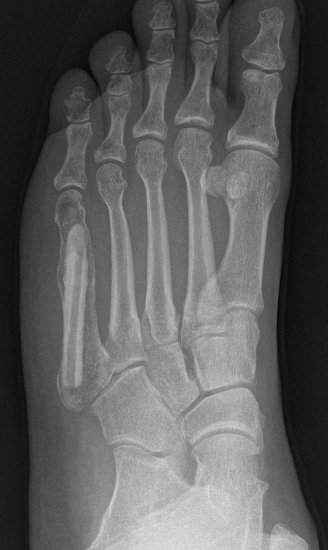

X-ray

Intralesional calcification - punctate, stippled calcification and broken rings

Hand / Foot

Foot